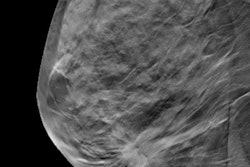

Unfortunately, digital mammography did not improve the detection of grade 3 cancers, Blank said.

"We were disappointed that digital mammography showed no increase in the detection of grade 3 invasive cancers," he told AuntMinnie.com. "These are difficult but important cancers to detect. Radiologists therefore need to explore the use of digital processing in more novel ways, or further explore the use other modalities such as MRI or ultrasound to increase sensitivity for these cancers."